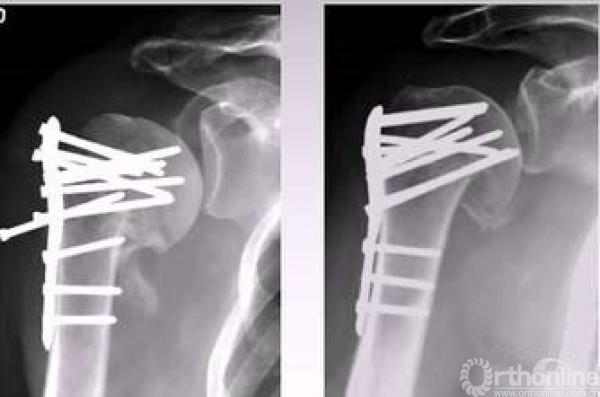

4.克氏针临时固定,用钢板压住骨折块。

以钢板进行复位,然后用皮质骨螺钉进行提拉 完成肱骨近端解剖形态。

解剖钢板与提拉螺钉的复位

需要注意:不要应用过度提拉,使得内侧肱骨距过复位。

注意完成内侧支撑和内外翻的复位。

在此病例中,为了复位良好,舍弃了肱骨近端与钢板贴服。